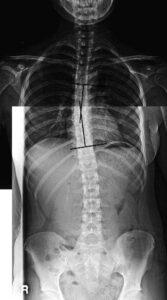

척추측만증과 추나요법

특발성 측만증의 질병의 특성상 조기 진단과 조기에 보존적 치료를 시행하는 것이 중요한데 실제 초등학교 대상으로 척추 검사를 해 보면 저학년의 경우에도 20-30% 정도는 측만증의 가능성을 보이는데 이 비율이 해마다 눈에 띄게 증가하고 있는 추세입니다.

측만증 치료의 목표는 만곡의 진행을 방지하고 척추의 균형 상태를 유지하며, 만곡을 방치하였을 경우 장차 발생될 수 있는 요통을 예방하며, 외관을 좋게 하는 것입니다. 한마디로 건강한 성장을 이루기 위한 기초적인 치료라 할 수 있습니다.